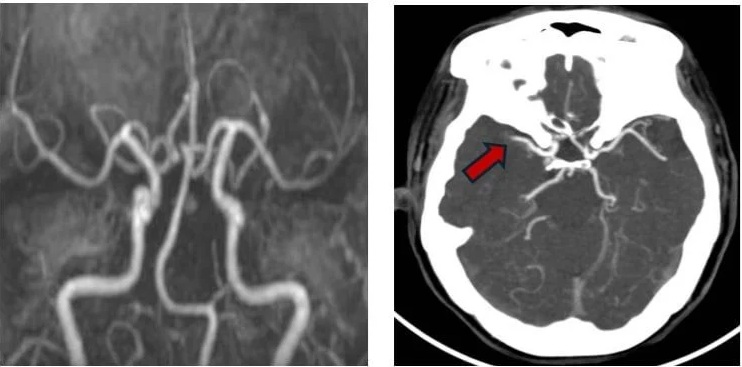

Lập tức, các bác sĩ tại Khoa Bệnh lý mạch máu não kích hoạt quy trình báo động đột quỵ nội viện. Chụp CT mạch máu não khẩn ghi nhận hình ảnh tắc động mạch não giữa bên phải – với hình ảnh huyết khối mới hình thành trong lòng mạch máu. Không để thời gian trôi qua vô ích, người bệnh được chuyển thẳng vào đơn vị can thiệp mạch máu thần kinh. Tại đây, quy trình can thiệp nội mạch được thực hiện khẩn trương và chính xác.